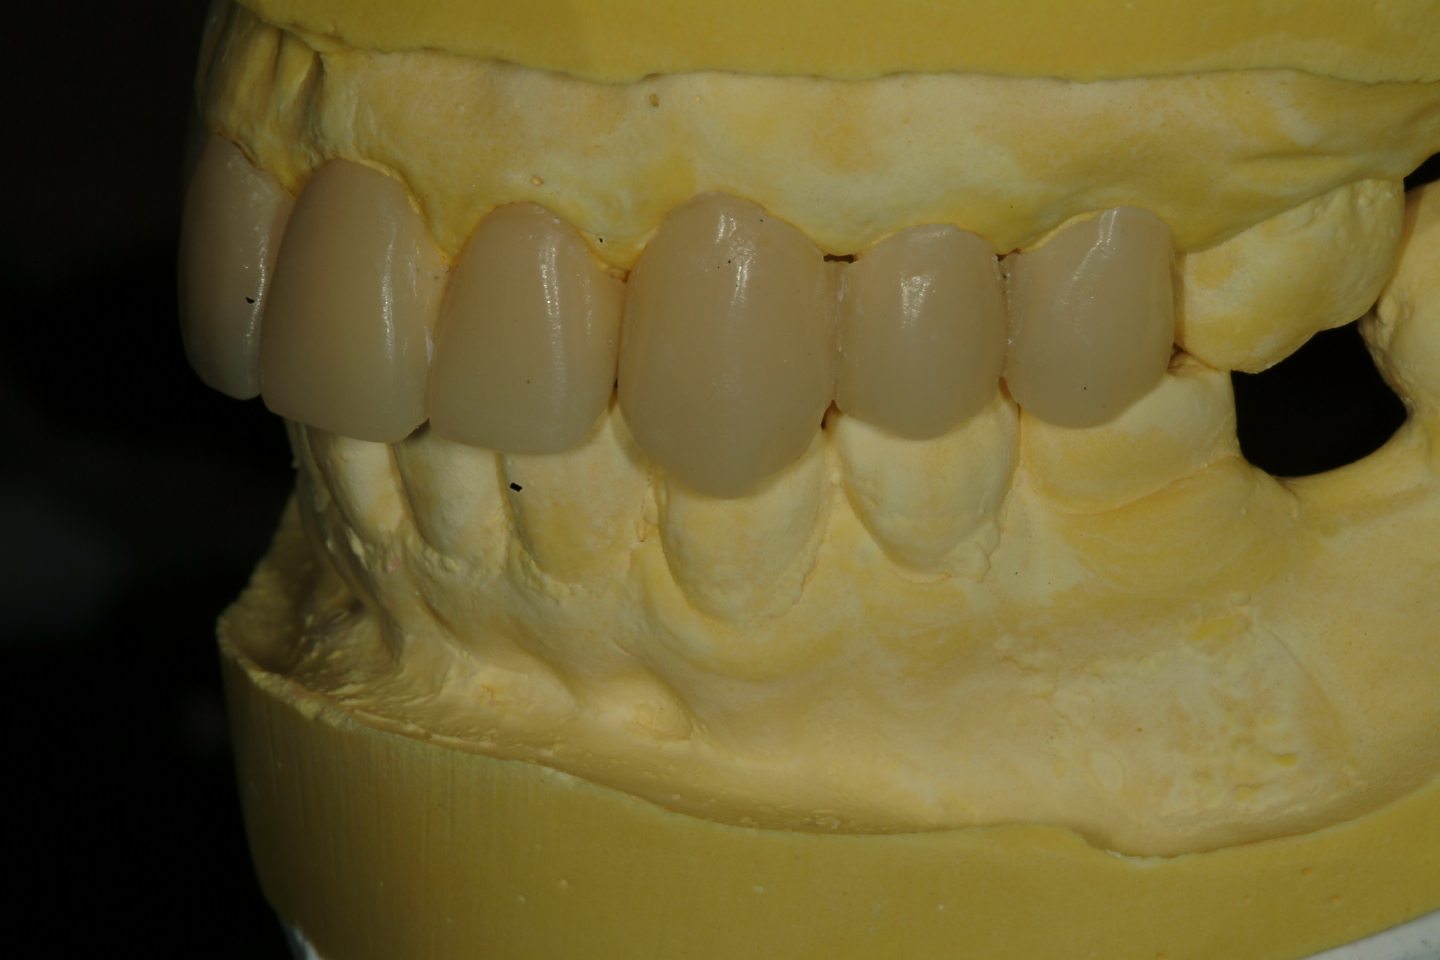

四、以臨時假牙模擬未來假牙外型(圖四)

圖四 |